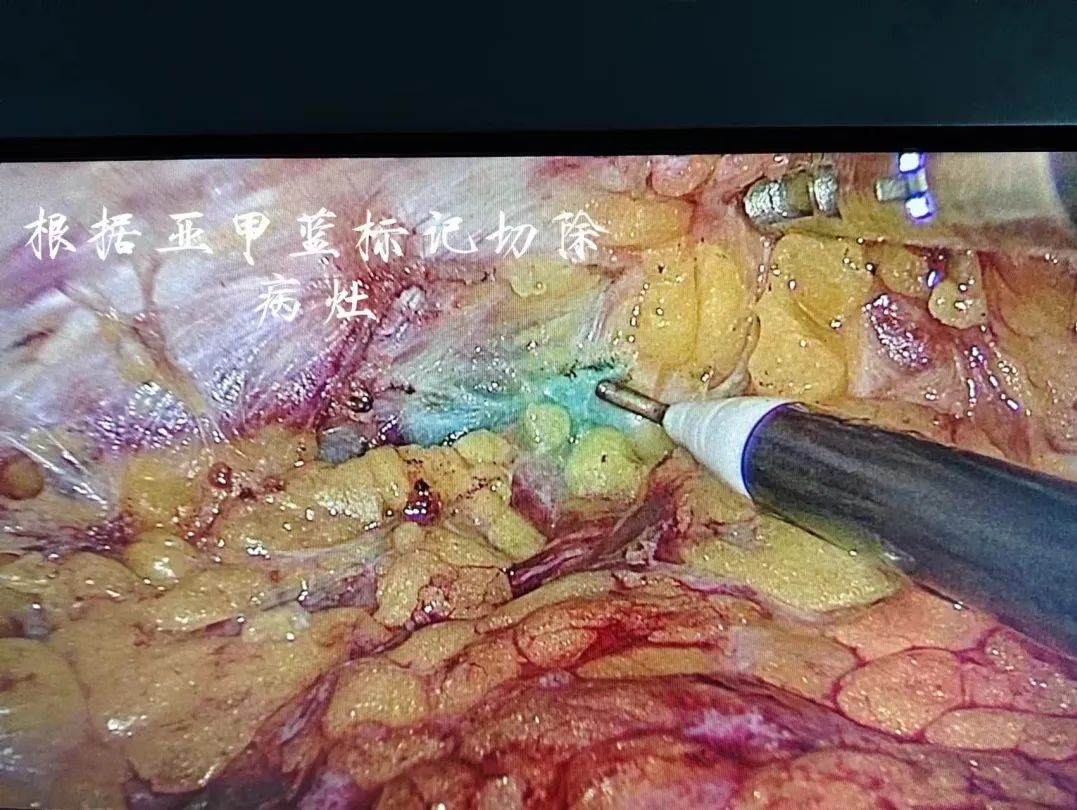

術(shù)前,用染色劑亞甲藍(lán)在乳腺腫瘤邊緣1cm環(huán)周注射標(biāo)記好手術(shù)的切除范圍內(nèi),僅取腋下皮紋3cm小切口,經(jīng)此切口完成了前哨淋巴結(jié)的切除活檢,以及腔鏡輔助下完成腫瘤的切除,胸部不留任何疤痕。術(shù)后3天,蘇女士順利出院,患者及家屬都對手術(shù)效果非常滿意。